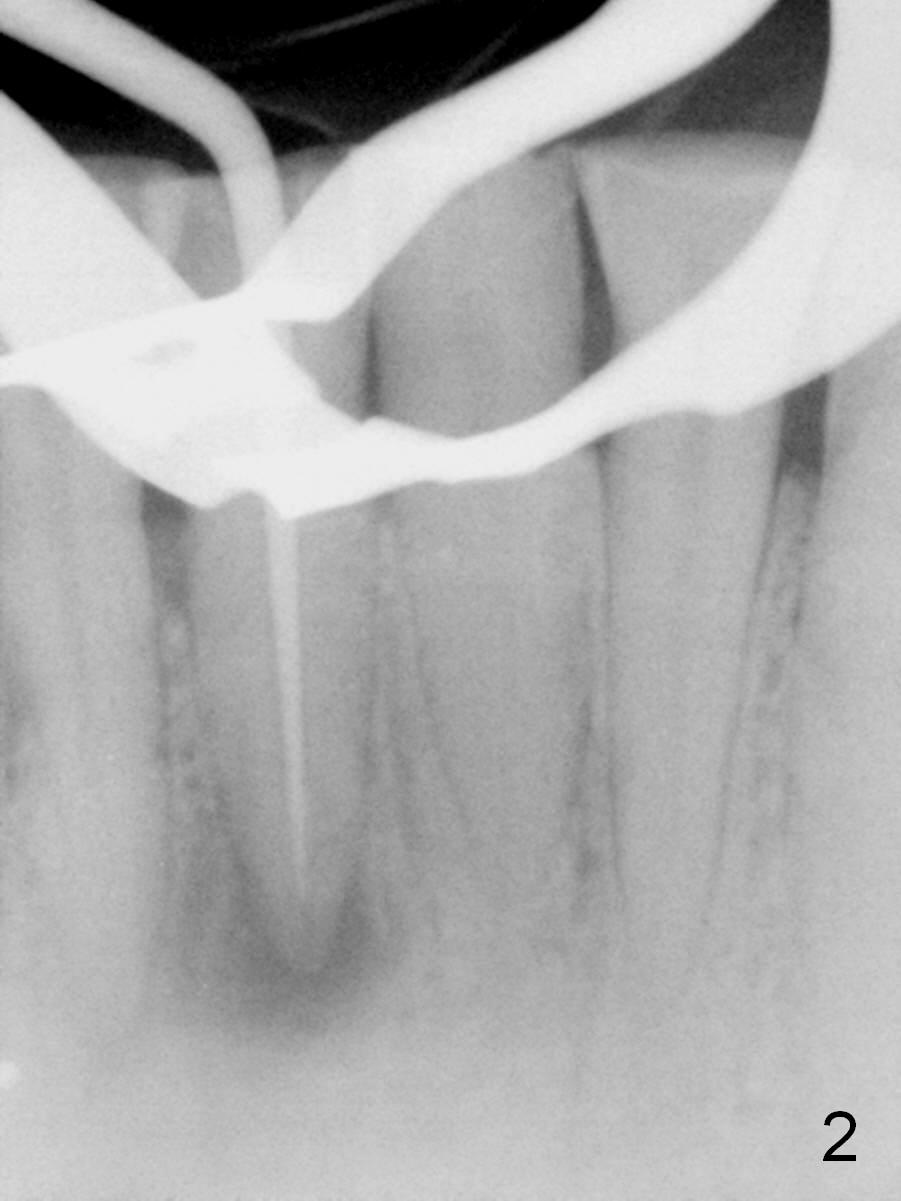

A 45-year-old man has had a chronic fistula associated with the tooth #25 (Fig.1). There is purulent discharge sometimes. After debridement with hand files #10-20 and rotary one 30/06, a master cone 30/.06 is inserted incompletely (Fig.2). After rotary files 30/.08 at 16.0 mm and 30/.10 at 15.0 mm and hand files 10-20 at 17 mm, the master cone is apparently inserted to the WL. With application of Endo Sequence Sealer (syringe), the master cone is reinserted (Fig.3). When the rubber dam is removed, the sealer is found to have expelled from the fistula. With an endo curette (Fig.5), the sealer is removed from the deepest portion of the sinus tract (apex of the tooth). What do you want to know the outcome of the supplementary surgical maneuver? The sealer is gone (Fig.6). The immediately supplementary treatment avoids a separate apicoectomy. No fistula is noted <2 weeks postop (Fig.7). The attrition is due to #8 and 9 veneers, fabricated 8 years earlier. The tooth #24 is symptomatic with loss of incisal composite nearly 4 years postop (Fig.8 <). After 30/.04 gutta percha (GP) try in (Fig.9), RCT is finished without accessory GP (Fig.10).